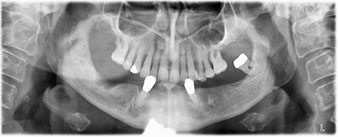

Un CT Scan à faisceaux coniques tridimensionnel (CBCT, Planmeca) a été réalisé au préalable afin de réduire les risques. Il a révélé une qualité et une quantité d'os disponible suffisante pour l'intervention chirurgicale et la restauration immédiate par la méthode All-on-four. En suivant le protocole de ce concept, les implants sont insérés au niveau de 35, 32, 42 et 45 en inclinant les implants distaux jusqu'à 45°, le profil d'émergence se déplace ainsi vers l'arrière et produit un polygone de stabilisation plus large (Fig. 3).